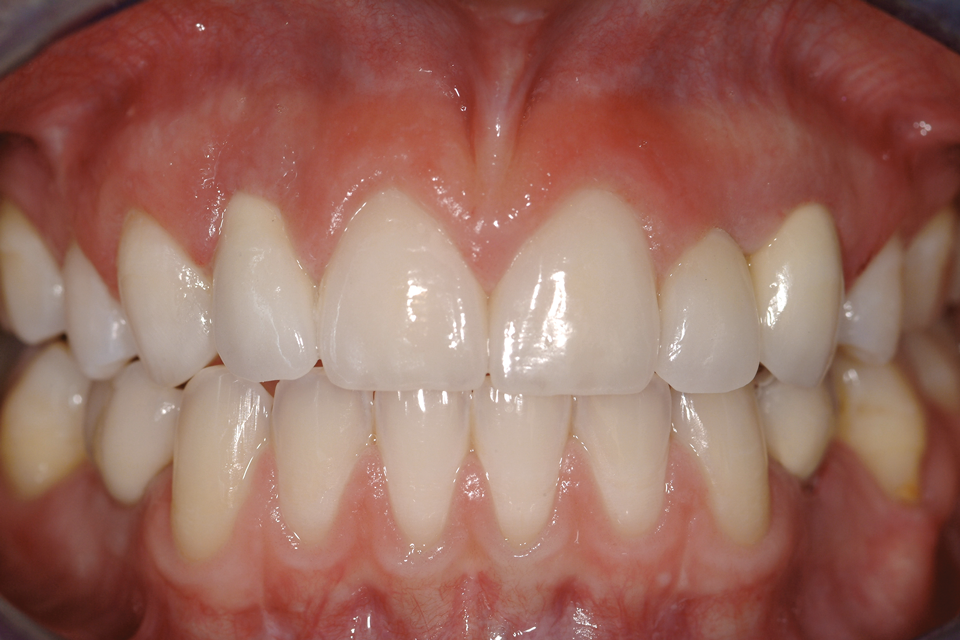

There are a number of requirements to achieve a successful bonded bridge. First, the edentulous site must be approximately the same width as the contralateral tooth. There also must be adequate soft tissue to provide esthetic emergence contours for the ovate pontic. Some clinicians may be concerned that the ovate pontic will not adequately maintain the soft tissue and, over time, the tissue will shrink away from the pontic. However, the soft tissue under an ovate pontic has been shown to be quite stable long-term.39 An example of this is shown in Figure 15.

Fig 15. Four-year postoperative photograph of zirconia bonded bridge replacing tooth No. 7.

Figure 15